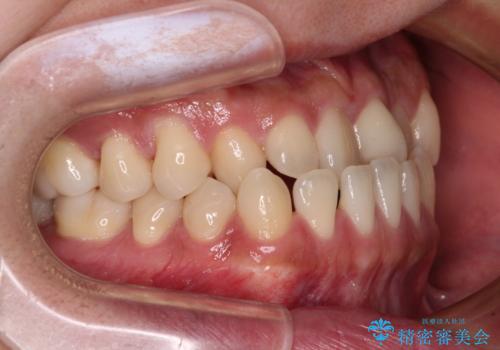

前歯のクロスバイトをワイヤー矯正で 結婚式までに治したい

- 前歯のクロスバイトを気にして来院された患者様です。

1年半後に結婚式が控えているとのことで、ワイヤー矯正で早めに治療を終えることを希望されました。

骨格的に下顎が前方に位置していましたが、歯列矯正で改善できると判断し、ワイヤー装置にて矯正治療を行うこととしました。

骨格的な左右差も顕著であったため、正中は合わず、上下前歯の一部が接触しない咬み合わせとなることが予想されましたが、正中はもともとのズレが小さかったことから、合わせることができました。